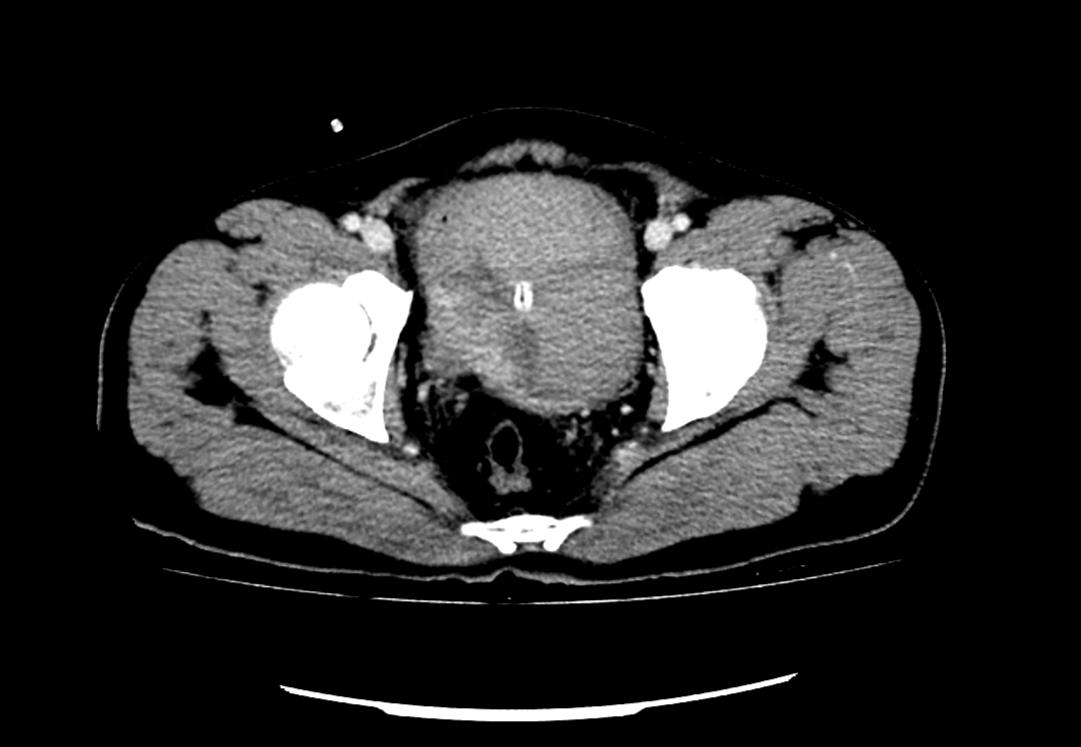

患者為53歲的男性,患者因肉眼血尿就診我院門診,行泌尿系CT考慮膀胱占位,建議患者住院治療,入院后完善膀胱MRI檢查進(jìn)一步診斷膀胱腫瘤,侵犯肌層。行膀胱腫物激光切除后,病理學(xué)檢查明確“膀胱高級別尿路上皮癌,肌層浸潤”診斷,結(jié)合泌尿外科診療指南建議行根治性膀胱全切術(shù)。

泌尿外科醫(yī)生團(tuán)隊術(shù)前將患者情況上報醫(yī)務(wù)科,并組織了多次會診。患者“肌層浸潤性膀胱癌”診斷明確,術(shù)前完善心肺功能排除無明顯手術(shù)禁忌,結(jié)合指南推薦及泌尿外科團(tuán)隊成員綜合意見,決定在全麻下行腹腔鏡下膀胱根治性切除+盆腔淋巴節(jié)清掃+回腸代膀胱手術(shù)。術(shù)前嚴(yán)格完善準(zhǔn)備工作,手術(shù)歷經(jīng)7小時,完整切除了患者的膀胱、前列腺及精囊,并行回腸代膀胱。手術(shù)順利,術(shù)后3天可正常行走,復(fù)查患者各項指標(biāo)正常。